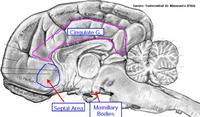

El tracto olfatorio termina por una bifurcación en la ESTRIA OLFATORIA MEDIAL y LATERAL, las cuales proyectan respectivamente al AREA SEPTAL (responsable de los reflejos olfatoviscerales) y a la CORTEZA PIRIFORME (responsable de la sensación consciente de la olfación).

El Sistema Límbico comprende a estructuras de la corteza cerebral que bordean el tronco encefálico, junto a ciertos componentes del hipotálamo, tálamo y epitálamo, y está relacionado con la percepción de las emociones de importancia para la supervivencia del animal, como la defensa, alimentación, escape, etc.. y emociones asociadas con la supervivencia de la especie, tales como la defensa territorial, cortejo, apareamiento, etc.., estando además relacionado con procesos relativos al aprendizaje y memoria.

HIPOCAMPO: Es una estructura de la corteza cerebral con 3 capas de células, llamada ARQUEOCORTEX, de importancia en aprendizaje asociativo y memoria (particularmente memoria de corto tiempo). Tanto pacientes amnésicos como animales con daños en hipocampo exhiben problemas tiempo-dependientes en tareas de comportamiento generalmente descritas como asociativas o relacionadas por naturaleza. Este área del cerebro tiene un bajo umbral de ataques o convulsiones.

CIRCUNVOLUCIÓN CINGULADA de la corteza cerebral. En general, la corteza cerebral tiene efecto depresivo sobre el comportamiento emocional. Esto se demostró provocando la llamada falsa rabia cuando se extirpó la corteza cerebral de perros o gatos, manifestándose con fustigamiento de la cola, vigoroso arqueamiento de la parte trasera, arañazos y mordeduras y respuestas autonómicas. Estas respuestas “de rabia” suceden espontáneamente o pueden producirse por la aplicación de simples estímulos.

AMIGDALA: Es una región altamente diferenciada cerca del polo temporal de los hemisferios cerebrales de los mamíferos. Es un núcleo basal que está implicado en la emoción, memoria, comportamiento social, comportamiento reproductor, miedo y agresión, y modulación de sistemas autonómicos y neuroendocrinos. Muchos de sus efectos son opuestos a los del septum. Lesiones de la amígdala pueden suponer comportamiento dócil, mientras que su estimulación produce comportamiento agresivo.

AREA SEPTAL o SEPTUM: este área de la corteza cerebral está envuelta en varios procesos fisiológicos y de comportamiento, tales como emociones, alivio del miedo, comportamiento dócil y estrés, además de en procesos de regulación autonómica ( ingesta de comida o agua, hibernación, etc..). Su estimulación lleva a un comportamiento dócil, y puede suprimir muchas respuestas autonómicas.

porción del TÁLAMO. Enlaza el sistema límbico al neocórtex y es como un filtro sobre qué información sensoria puede acceder al sistema límbico.

LÓBULO PIRIFORME del RINENCÉFALO. Entra dentro del sistema límbico ya que tiene funciones afectivas junto a otras estructuras límbicas tales como impulsos o ciertas conductas de comportamiento.

CUERPOS MAMILARES DEL HIPOTÁLAMO. Su conexión con otras estructuras límbicas se demuestra porque su estimulación produce mucho de los cambios de comportamiento que ocurren al estimular otras zonas del limbo.